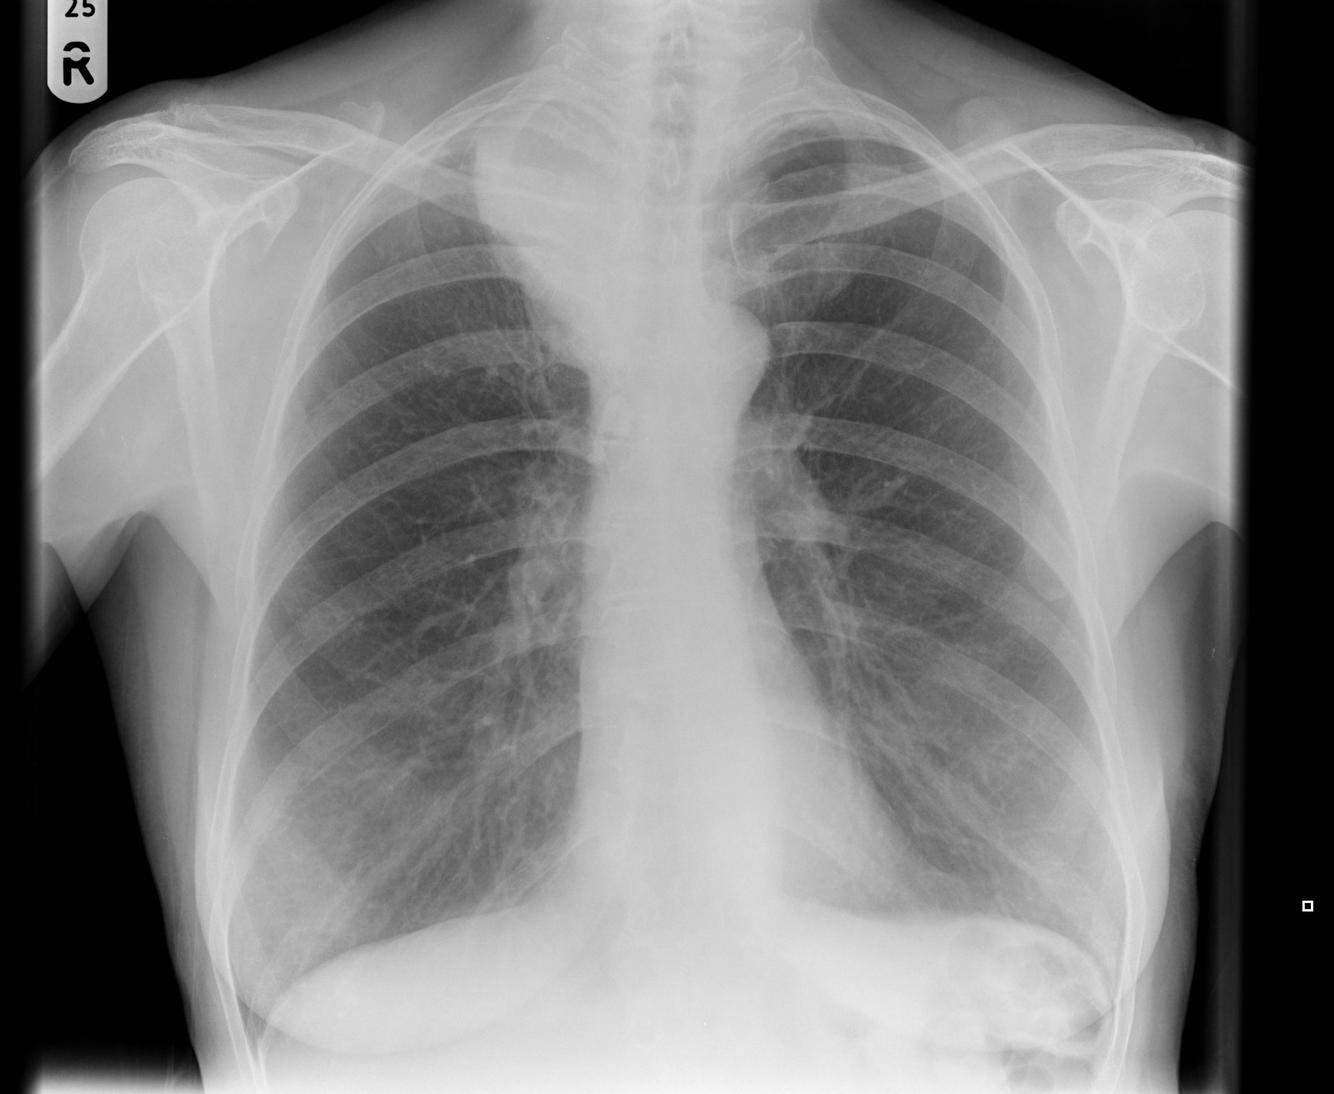

Consolidation

opacification with air bronchograms

e.g cancer, pneumonia, haemorrhage, edema